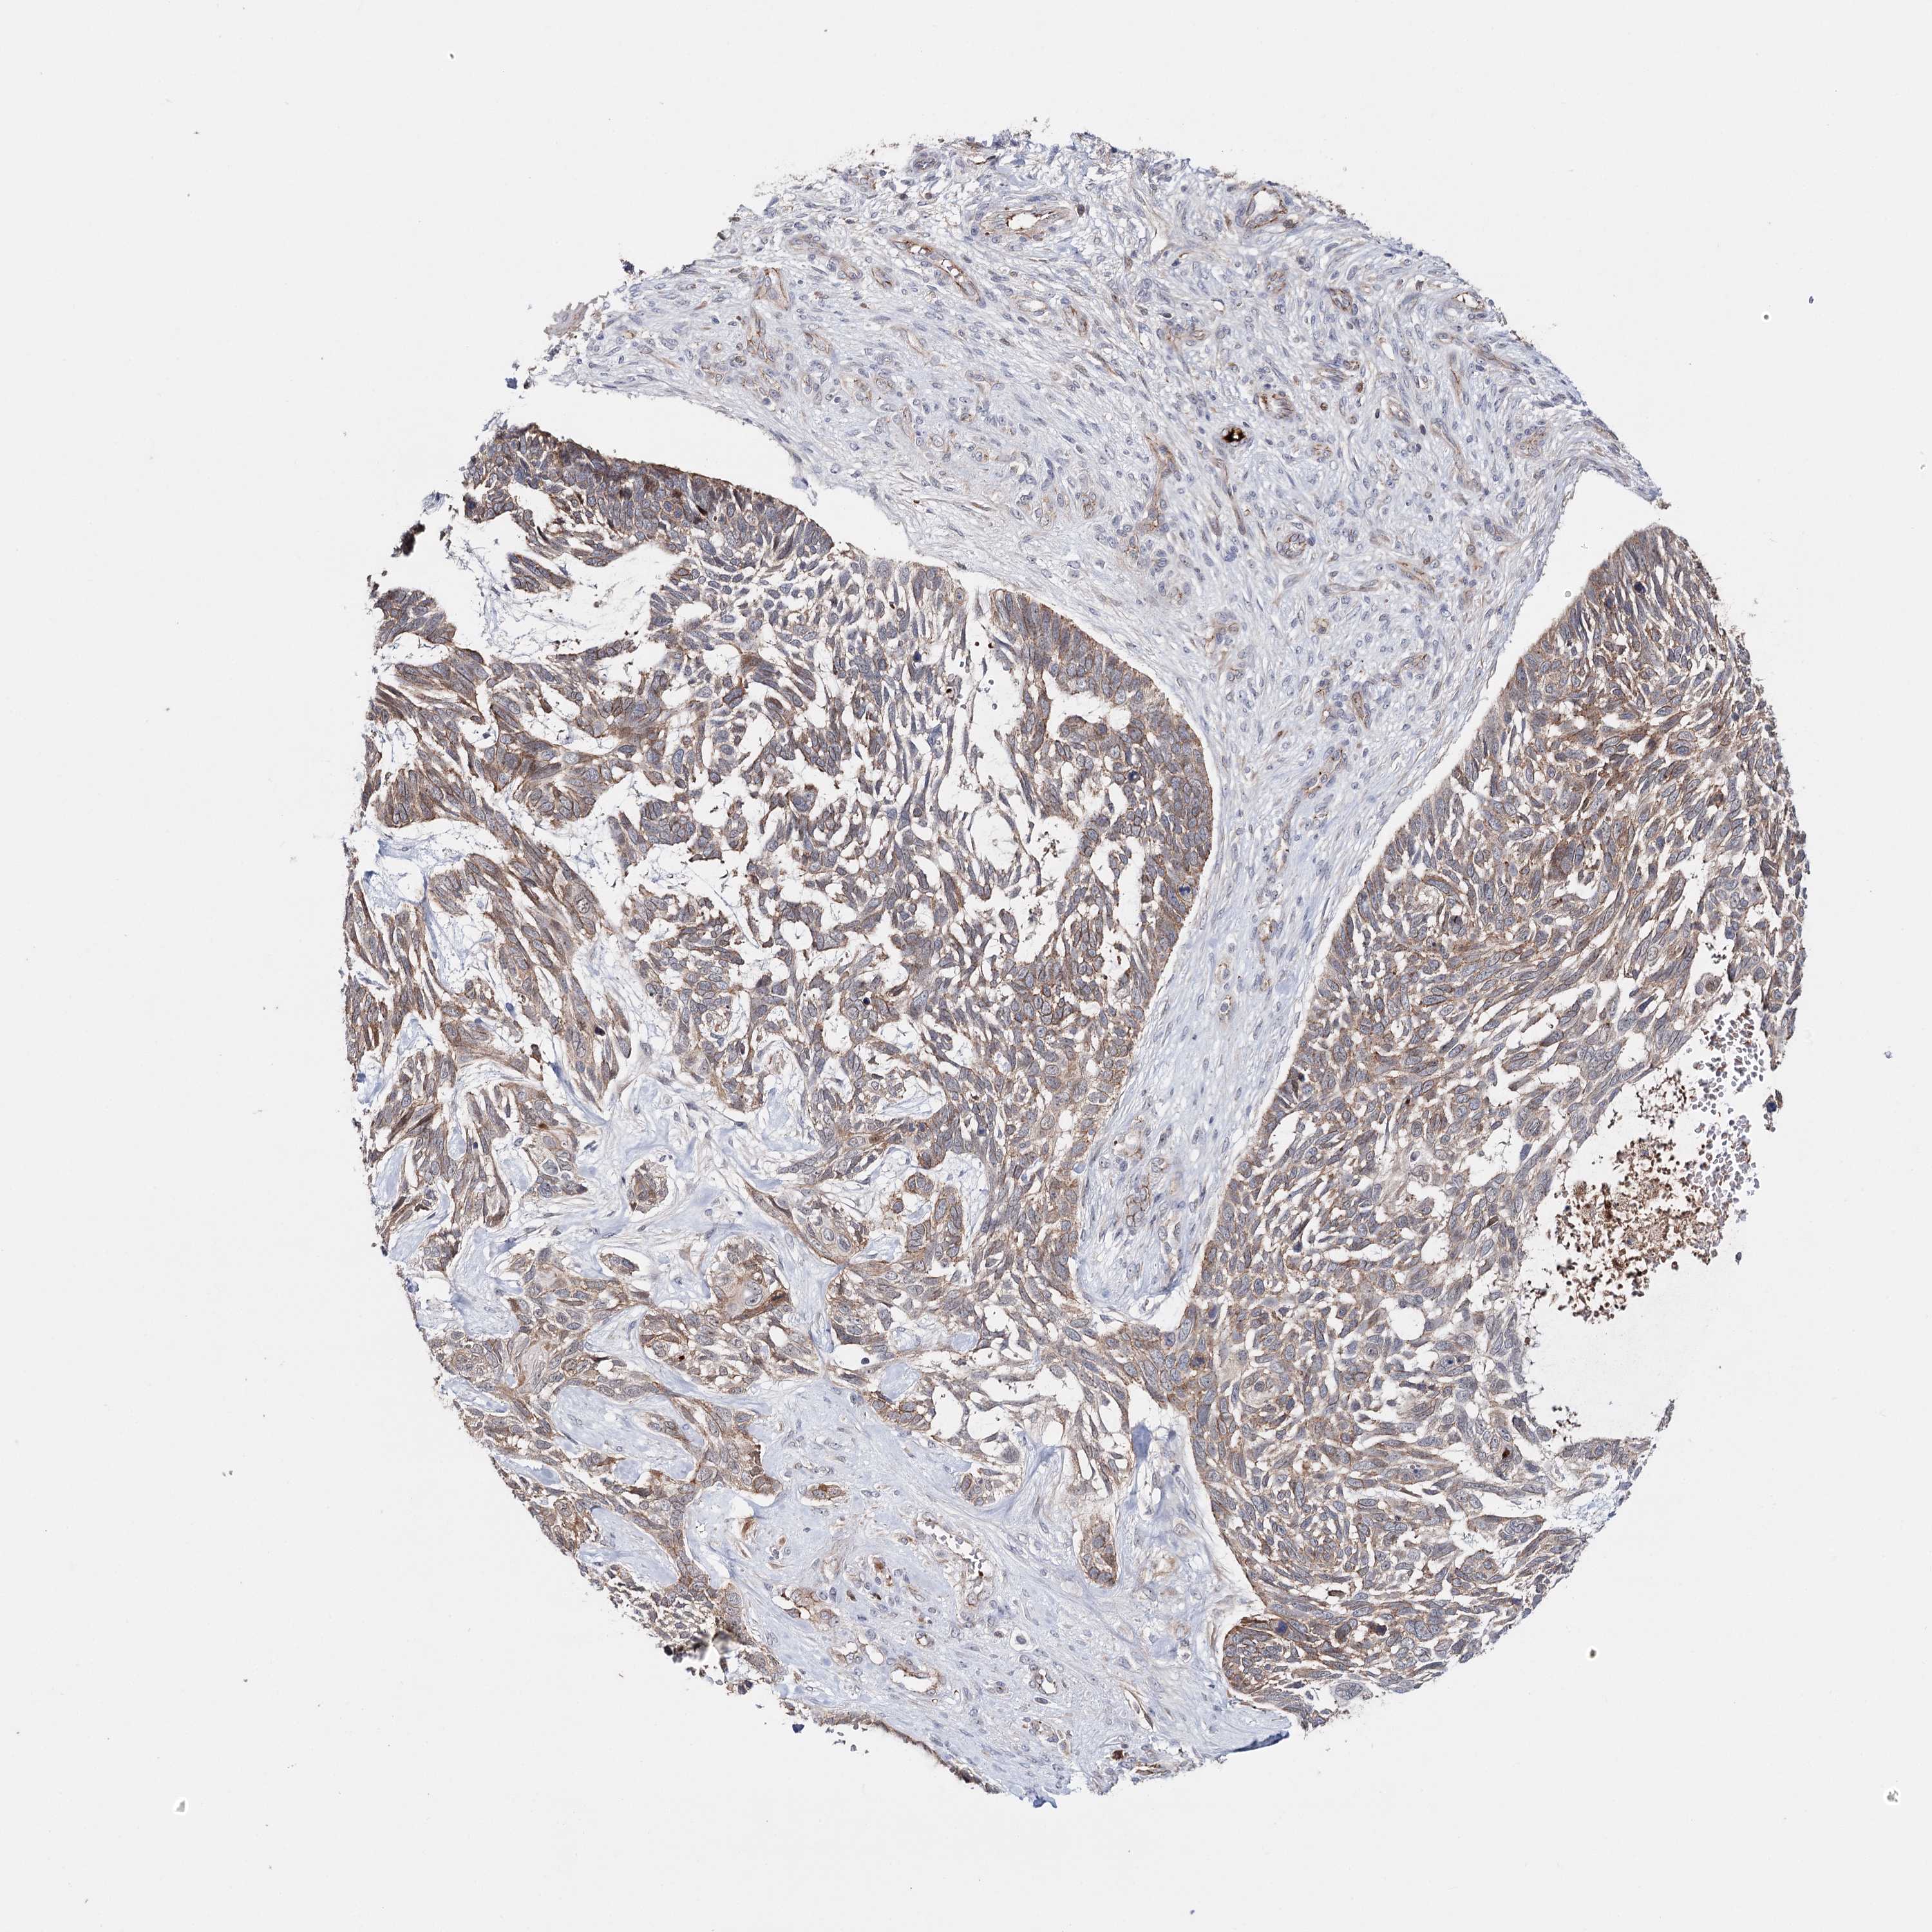

SKIN CANCER - Protein expressioni

A mouse-over function shows sample information and annotation data. Click on an image to view it in a full screen mode. Samples can be filtered based on level of antibody staining by selecting one or several of the following categories: high, medium, low and not detected. The assay and annotation is described here.

Each image is clickable and will lead to virtual microscopy that enables deeper exploration of all samples and also displays staining intensity scores, fraction scores and subcellular localization as well as patient and tissue information for each sample.

Antibody CAB037334

Staining

Squamous cell carcinoma, metastatic, NOS